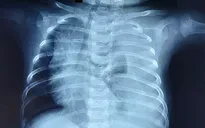

Cứu bé 3 tháng tuổi phổi trắng xóa vì rò dịch dưỡng chấp

VTV.vn - Chỉ nặng 5kg, bé 3 tháng tuổi bị rò dịch dưỡng chấp hơn 500ml mỗi ngày buộc các bác sĩ phải tiến hành nội soi thắt ống ngực.